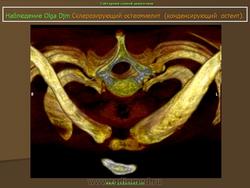

Склерозирующий остеомиелит из ключицы впервые был описан как заболевание лица в 1974 году. Существует боли и часто локализуется опухоль из медиальной трети ключицы, с повышенной плотностью радио.Sternoclavicular совместных, как правило, никогда не занимался. Он также известен как асептический расширения остеосклероз из медиального конца ключицы.

Множественные мелкие и крупные (до 10 мм) очаги остеосклероза округлой или овальной формы, расположенные в эпифизах трубчатых костей, а также в других костях, за исключением ключицы.